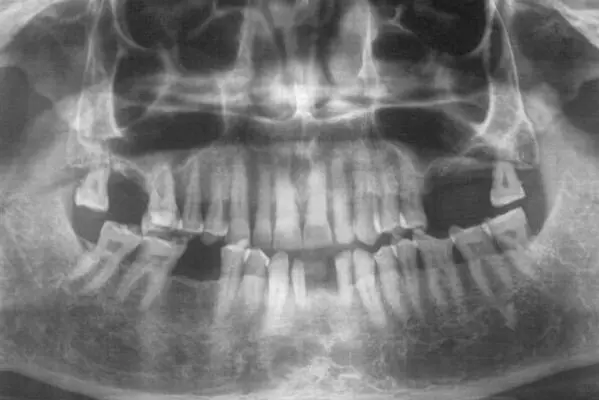

Maxillary Sinus Graft

Nasal Floor Elevation

Sinus Graft

There are two types of sinus graft procedures:

[1] Indirect Sinus floor Elevation with placement of implant

[2] Direct Sinus Graft using modified caldwell luc technique

The maxillary sinuses are behind your cheeks and on the top of the upper teeth. Sinuses are like empty rooms that have nothing in them. Some of the roots of the natural upper teeth extend up in to the maxillary sinuses. When the upper teeth removed, there is often just a thin wall of bone separating the maxillary sinus and the mouth. Dental implants need bone to hold them in place. When the sinus wall is thin, it is impossible to place dental implants in this bone.

There is also a solution, its called sinus graft or sinus lift. The specialist or skilled implantologist enters the sinus from where upper teeth used to be. The thin paper like sinus membrane carefully lifted upward and donor bone is inserted into the floor of sinus. After several months of healing, the bone becomes the part of the patient’s jaw and dental implant can be inserted and stabilized in this new sinus bone.

Furthermore, If enough bone between the upper jaw ridge and the bottom of the sinus available to stabilize the implant well, sinus augmentations and implant placement can sometimes be performed as a single procedure. If enough bone is not available sinus augmentation will have to be performed first, then the graft will have to mature for several months, depending upon the type of graft material used. Once the graft material has matured, the implant can be placed.